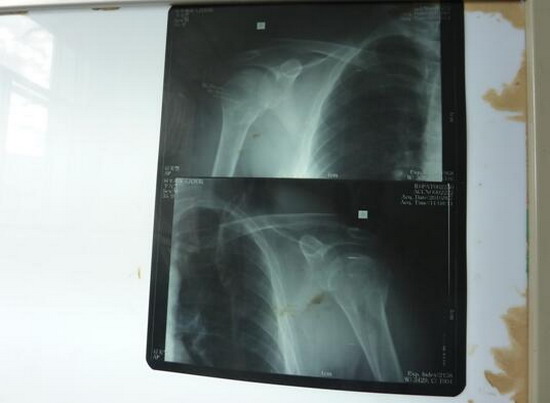

肱骨外科颈及肱骨头骨折切复内固定